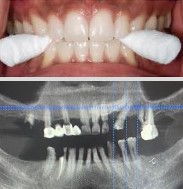

Planning Partially Edentulous

What we need from you?

CBCT

DICOM FORMAT

NO CD WITH VIEWER

INTRAORAL SCAN

MAKE SURE THERE ARE NO HOLES ON SCAN.

CAPTURE AS MUCH SOFT TISSUE AS POSSIBLE AND FULL PALATE

PATIENT’S PORTRAIT PICTURE SMILING, RESTING AND RETRACTORS